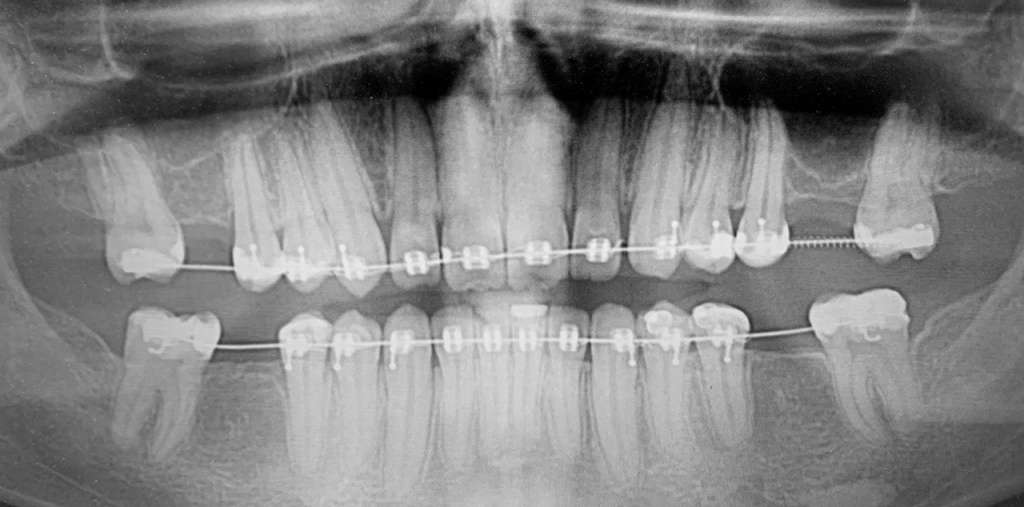

По результатам диагностики принято решение провести синус-лифтинг с помощью боров SinPro. В ходе вмешательства установлены имплантаты AnyRidge и AnyOne с первичной стабилизацией 40 Ncm.